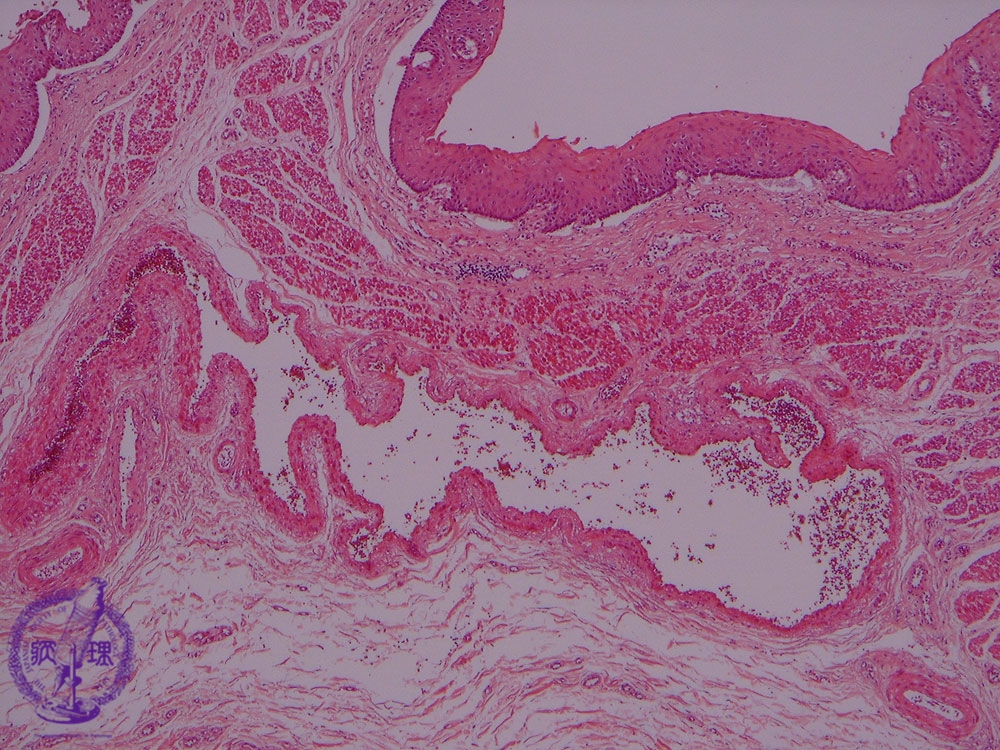

Microscopic view (H&E stain, low power): Esophageal submucosal veins are strikingly dilated (circle) and their walls are thickened (arrow).